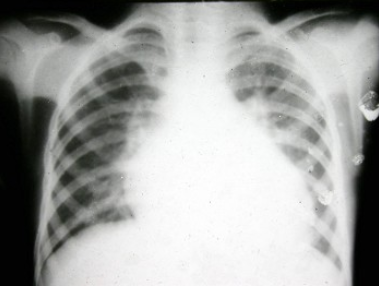

81、单项选择题

男,10月。有时哭闹。X线检查如图,最可能的诊断为()

A.畸胎瘤

B.胸腺瘤

C.婴幼儿胸腺

D.右上肺不张

E.神经母细胞瘤